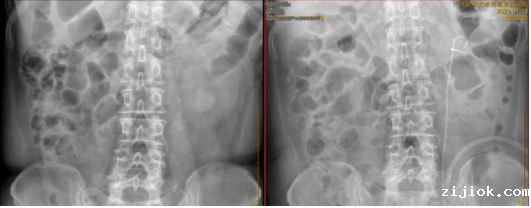

肾结石术后(左)、术前(右)

医院对患者进行B超检查,发现其右肾萎缩,左侧输尿管上段结石(1.4*1.1*2.0cm),左肾结石(约2.5*1.5*2.0cm),血肌酐:CREA 878 μmol/L,泌尿系CT提示左肾下盏结石体积较大,且IP角(肾下盏漏斗夹角)较小。最终诊断为急性肾功能不全、侧输尿管上段结石和左肾结石,需要手术清除结石。

1月17日下午,正式开始手术治疗。常规经皮肾镜(PCNL)处理超小ip角下盏结石时,需要在肾脏打一个直径2cm的洞,受空间限制,结石也无法完全清除。而本次手术采用针式肾镜联合输尿管软镜碎石取石术不但清除了所有结石,而且手术结束后,直接拔出穿刺针即可,患者皮肤仅留下一针眼,创伤极小。患者术后第二天即可出院。